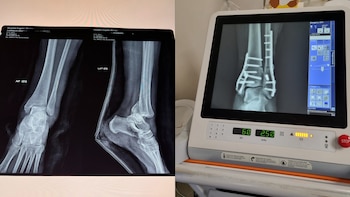

Quando a mulher chegou ao hospital, ela foi submetida a uma cirurgia tíbia quebrada, fíbula e calcâneoonde foram colocados duas placas e 16 parafusosportanto, prevê que não será uma lesão que cicatrizará em menos de 15 dias e exigirá um período de imobilização, que terá dificuldades para trabalhar e cuidar dos filhos, além de ter que fazer reabilitação posteriormente.

“Peço que seja amplamente divulgado. Tenho o raio-x, tenho o raio-x com a placa, tenho o vídeo do acidente onde vocês podem ver exatamente como funciona aquele lugar, vocês podem ver exatamente como, minha perna está quebrada em vários lugares”, confirmou.